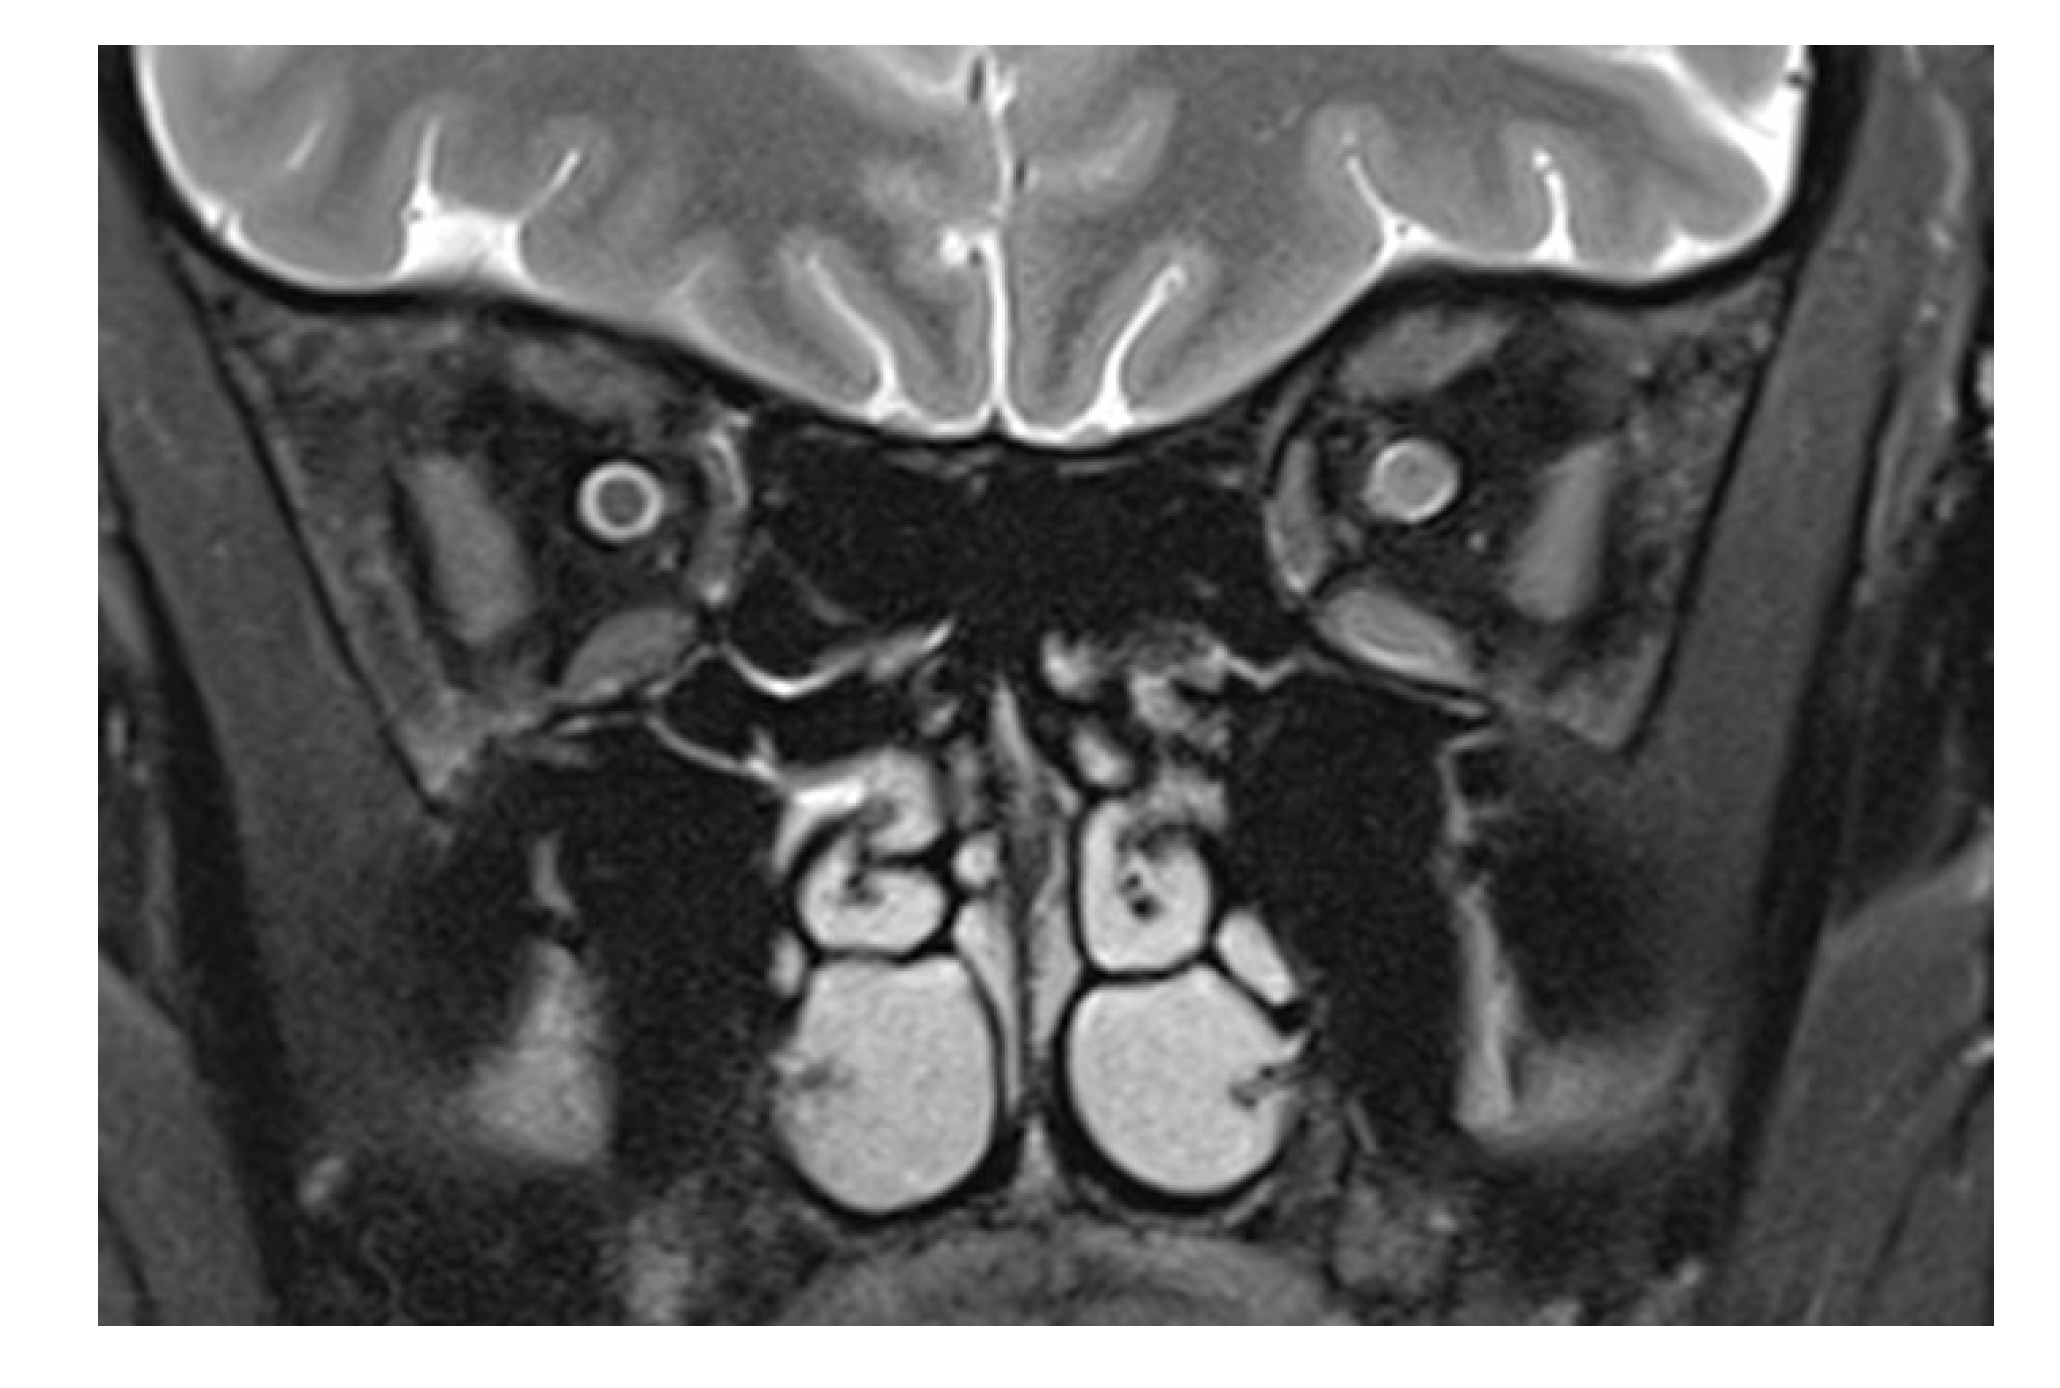

Figure 2.

T2-weighted frontal image in a multiple sclerosis patient with optic neuritis. While the subarachnoid space has a normal diameter on the left, an enlarged optic nerve encroaches in the same space, recognizable by the smaller liquor-filled rim of the nerve. Leakage of cerebrospinal liquor after direct laceration of the sheath, however, cannot be counted out. The diffuse signal increase of the nasal retrobulbar space in Figure 1f,g may be explained by cerebrospinal liquor leaking from an injured optic nerve sheath and by edema.

The patient presented here had direct trauma to the right eye, and MRI was performed after full ophthalmological examination, only hours after the trauma in a conscious and cooperative patient. The trauma was a “perforating stab wound” [4] but missing the globe. The only sequela clinically visible was a conjunctival tear. CT excluded soft tissue changes, fracture, and foreign bodies in the globe and orbit. On MRI, changes in the optic nerve (and impossible to be seen on CT) were noted. This structure showed an opacification of the subarachnoid space, compatible with hemorrhage: an increase in the T2 signal of the optic nerve anterior to the inner opening of the optic canal; an increase in signal intensity on the diffusion-weighted b1000 image; and a decreased signal in the ADC map in the same location. The obliteration of the subarachnoid space around the optic nerve was different from what is commonly seen in the enlargement of an optic nerve. (For comparison, Figure 2 shows a T2-weighted image of an inflamed optic nerve in a patient with multiple sclerosis. There, the nerve supplants the subarachnoid space, which in comparison to the right and unaffected side is less wide).